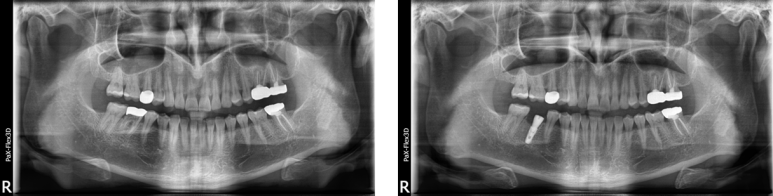

49세 남성

하악 임플란트 케이스

(전) 2021-08-18 (후) 2022-09-14